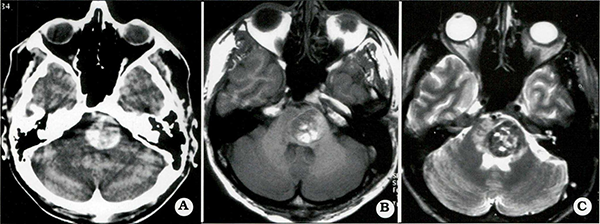

Finalmente, las lesiones ubicadas en el vermis o hemisferios cerebelosos, piso del cuarto ventrículo y superficie dorsal del bulbo raquídeo y protuberancia pueden ser adecuadamente abordadas a través de una craneotomía suboccipital. Los autores efectúan este abordaje en posición prono, abriendo el foramen occipital, La retracción de las amígdalas cerebelosas permite exponer el vermis delcerebelo, Para la resección de las lesiones ubicadas en la superficie anterolateral del bulbo raquídeo se utiliza el abordaje suboccipital lateral extremo (Fig, 4), El grado de agresividad con este abordaje puede variar desde la simple exposición y/o esqueletonización del seno sigmoideo y bulbo yugular a la resección parcial del cóndilo occipital con movilización de la arteria vertebral. Estas medidas no siempre son necesarias; en general, un abordaje más limitado permite la resección total en la mayoría de los casos.

Fig. 4.

Pacientefemenina de 29 años que presentó disartría progresiva A) Imagen T-1 sagital, B) Imagen axial. Esta lesiónfue resecadapor vía lateralposterior extrema. Este paciente tuvo un déficittemporario de los nervios craneales bajos (IX, X. XI).